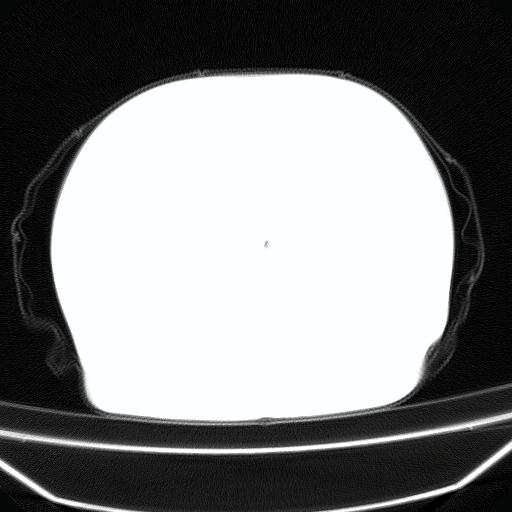

以下是引用liuyue在2008-4-19 22:25:00的发言:[br]先考虑:1.心衰伴肺水肿、双侧胸腔积液、叶间积液、双下肺不完全性肺不张; [br] 2.冠状动脉粥样硬化。

以下是引用lijuanln在2008-4-19 23:05:00的发言:[br]两侧胸腔积液,肺水肿[br]心包积液[br]提示心衰

以下是引用jiangjing在2008-4-20 10:43:00的发言:[br]结合病史支持 冠心病[冠状动脉钙化],心功能不全,肺淤血、肺水肿,双侧胸腔与斜裂积液